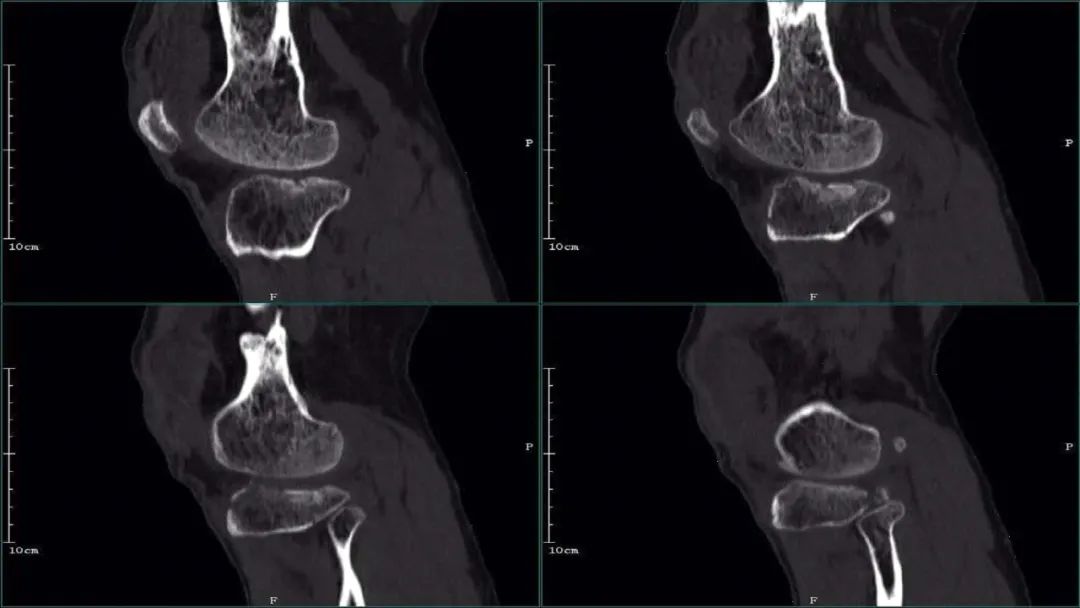

②CT 医学百科网 | YxBaike.Com

医学百科网 | YxBaike.Com

医学百科网 | YxBaike.Com ③治疗后 X 线表现

X 线及 CT:胫骨平台内、外侧平台骨皮质均不连续,见多发骨折线影,胫骨干与干骺端分离。